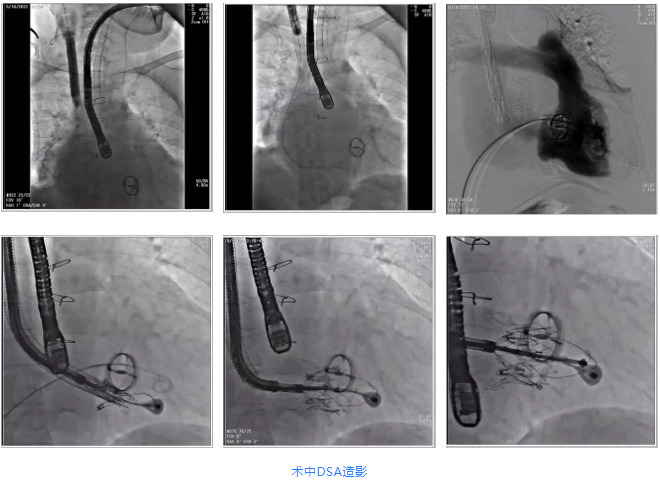

根據(jù)術前評估結(jié)果,郭應強教授團隊為患者量身定制了手術策略,決定使用LuX-Valve Plus經(jīng)血管三尖瓣置換系統(tǒng)開展手術治療。手術在全麻下進行,采用經(jīng)右側(cè)頸靜脈入路,在經(jīng)食道超聲和DSA的指引下調(diào)整輸送器角度以達到正確位置,勾住前瓣后逐步釋放盤片,盤片打開后順利扎針,最終完成瓣膜植入,輸送器撤出。術后超聲提示人工三尖瓣同軸性良好,瓣架固定牢靠,無反流和瓣周漏,術后三尖瓣平均跨瓣壓差為1 mmHg。